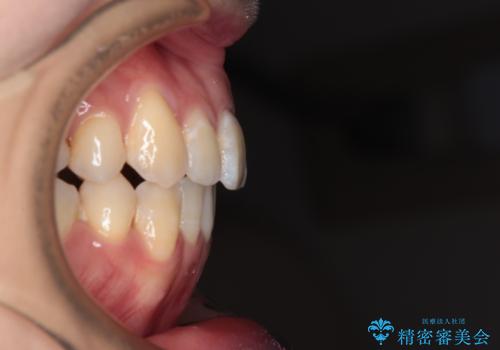

八重歯と開咬の抜歯矯正 ワイヤー装置を併用したインビザライン矯正治療

- 咬み合わない前歯と八重歯などのデコボコを気にして来院された患者様です。

上下前歯の位置を比較すると上顎が前方にあり、デコボコ改善でより上顎が前方に行く可能性があります。

開咬の改善にはインビザラインが有効であり、インビザライン単体での治療を検討しましたが、上顎前突を回避するために上顎左側第一小臼歯抜歯を行うこととしたため、補助装置とワイヤー矯正を併用した上で、インビザラインによる矯正治療を行うこととしました。